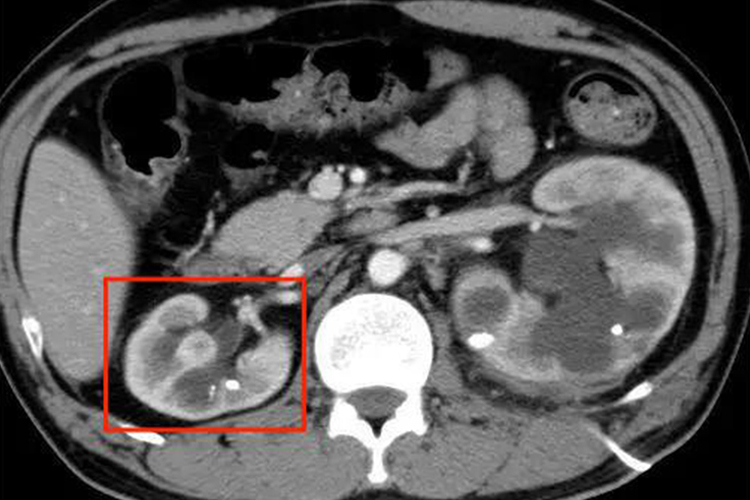

肾压迫性萎缩可表现为肾体积减小,重量减轻,色泽变深,同时可见肾盂扩张、肾盏融合消失,肾实质受压变薄,肾乳头变平或消失,皮质、髓质分界不清等表现。

肾压迫性萎缩是由于肾周围组织与器官长期受压,使得受压组织和细胞缺氧、缺血所致,如肿瘤推挤压迫,可致邻近正常肾组织萎缩,尿路梗阻时肾盂积水,可压迫周围肾组织,引起肾皮质、髓质萎缩。